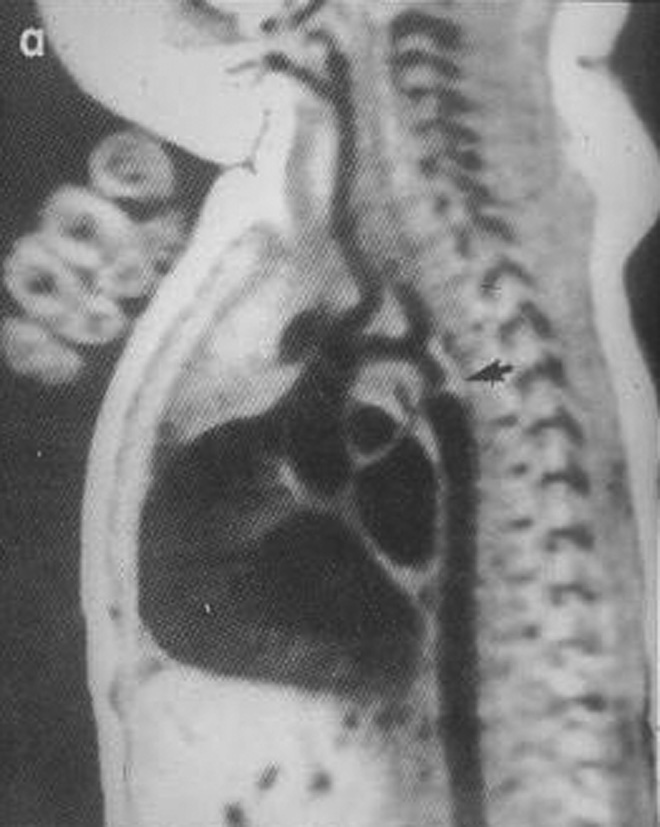

La coarctation préductale (c’est-à-dire située en amont de l’émergence du canal artériel ou ductus arteriosus), ou sténose de l’isthme de l’aorte, est une forme grave de la coarctation aortique, symptomatique dès les premiers jours de vie, mais les symptômes n’apparaissent qu’au moment de la fermeture du canal artériel. La chirurgie est urgente (figures 1 et 2).

Les cardiopathies complexes sont fréquentes, très polymorphes (ventricule unique, atrésie tricuspide, truncus arteriosus ou tronc artériel commun, etc.). Elles associent à des degrés divers cyanose et défaillance cardiaque suivant les cas (cf. figure 2).